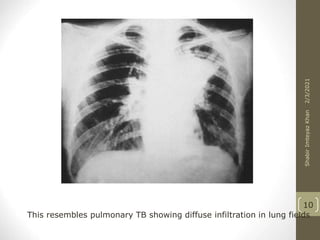

This resembles pulmonary TB showing diffuse infiltration in lung fields